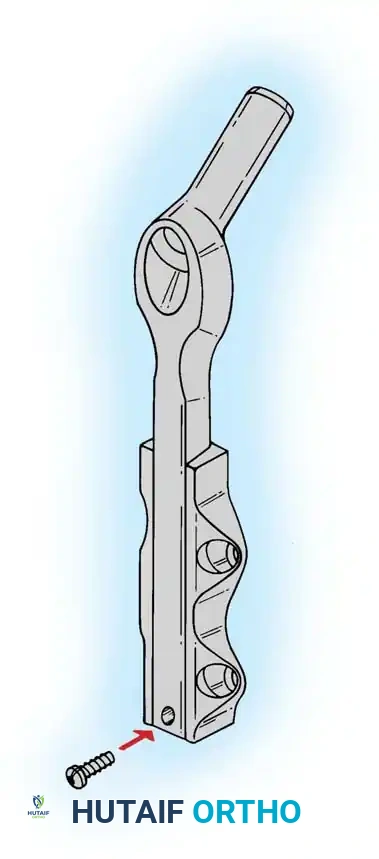

Implant Selection: SHS vs. Cephalomedullary Nail

- Sliding Hip Screw (SHS): The gold standard for stable intertrochanteric fractures (Evans Type I, AO 31-A1). The SHS allows controlled dynamic collapse along the axis of the femoral neck, compressing the fracture site and promoting primary bone healing.

- Cephalomedullary Nail (CMN): The implant of choice for unstable patterns, particularly reverse obliquity (AO 31-A3) and fractures with subtrochanteric extension. The intramedullary position of the nail decreases the lever arm of the implant, reducing bending moments and the risk of hardware failure.

Biomechanical Pearl: In reverse obliquity fractures, an SHS is contraindicated. The sliding mechanism of the SHS allows the femoral shaft to medialize uncontrollably due to adductor pull, leading to catastrophic failure. A cephalomedullary nail acts as a lateral buttress, preventing this medialization.

Finally, distal locking screws are placed to control rotation and maintain length.